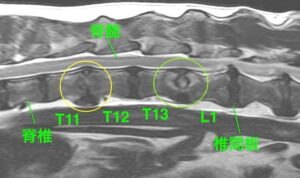

MRI検査では、胸と腰の間にある椎間板および軟骨に左の画像では周囲より白く、右の画像では周囲より黒くなっている病変を認めた(黄緑丸)

→これらの画像から胸と腰の間の椎間板脊椎炎が疑われる